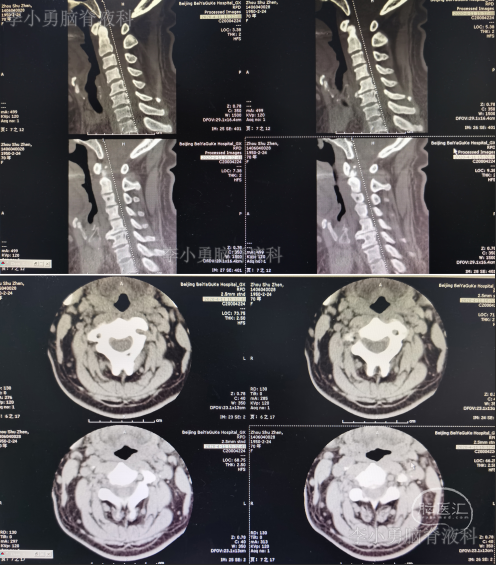

患者因间断性头晕、行走不稳,伴双上肢放射痛,麻木,于2020年4月11日入住北京某三级医院的中医骨伤科,当日查颈椎CT示椎管狭窄性颈椎病(图-1)。

图-1:2020年4月11日颈椎CT

图-2:2020年4月12日颈椎MR